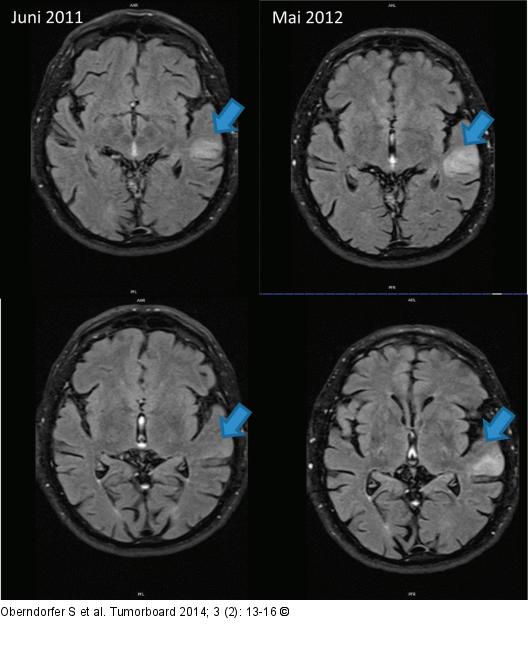

Abbildung 1: Glioblastom MRT/FLAIR vom Juni 2011 (radiologische Erstdiagnose) und präbioptisch im Mai 2012: zunehmende hyperintense Signalalteration links temporal (blauer Pfeil) |

MRT/FLAIR vom Juni 2011 (radiologische Erstdiagnose) und präbioptisch im Mai 2012: zunehmende hyperintense Signalalteration links temporal (blauer Pfeil) |